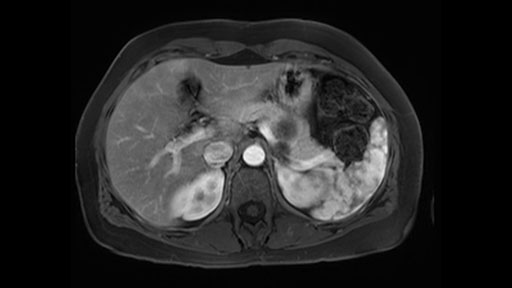

The lesion itself is quite adjacent to and abuts the splenic vein and therefore we need to anticipate that these two structures will be intimately related and possibly impossible to separate between the two.

The lesion also is quite posterior. While the plane between the cyst and the left adrenal gland is often preserved, we do have to pay attention here so that we remain in the right plane and maintain our margin here. Occasionally in these cases, en bloc adrenalectomy needs to be performed.

The third consideration in a distal pancreatectomy is whether I take the spleen or preserve it and I will try to always preserve it if I can. If it can be done safely and without too much difficulty or risk of bleeding. So the couple of considerations on the imaging that I look at is: Is the tail of the pancreas firmly embedded in the hilum of the spleen? I can see here that it isn’t and that it would likely be possible to preserve the spleen and I also look at the vessels and see whether the vessels are kind of firmly kind of intertwined in the distal part of the tail or whether we think we can actually separately take them with a stapler and remove all the tip of the tail of the spleen. So I think this would be a good candidate for a Warshaw technique, which is not preserving the splenic vein or artery but rather taking them as a segment and preserving the spleen. After this, the spleen would be getting all the blood supply from the short gastrics of the stomach. So that’s the third consideration in a distal pancreatectomy and the final thing is the retroperitoneum.

Sometimes with even benign lesions of the spleen you can have quite a lot of inflammation in the retroperitoneum and so I do think about and wonder whether I will have some difficulty in the retroperitoneum and I usually look at the scan for that purpose. It looks like there is no inflammation in the retroperitoneum. It does look very close to the patient’s left adrenal gland but knowing the planes and suspecting that there isn’t any active inflammation, this should be able to come off the left adrenal gland without any difficulty. But obviously prepared to take some of the left adrenal if that’s necessary in this procedure. So those are my procedure-specific slowing down moments in a distal pancreatectomy when I’m considering a laparoscopic approach. I think the patient-specific slowing down moments in this particular case I have discussed with the procedure-specific moments. I don’t really see any other issue or that I have to be careful of or consider.

The preoperative MR is very very important; any scan for that matter. Whether it is a pancreatic protocol CT scan or the MR as presented, the diagnostic imaging plays a very big role. And with this we see that it’s a very well-defined cystic focus in the body of the pancreas. Although there are septal enhancements, very well demarcated, but there is no vascular involvement. However, the mass appears to be in contact with the splenic vessel, and the mass is also a little bit in touch with the left adrenal and also the loop of bowel. So looking at this, basing on the features, I think it’s probably a mucinous cystic lesion, it could possibly be a pseudocyst. But basing on the history, it appears like there is no history that would point out to a pseudocyst. And not an IPMN as well; I don’t see any side branches from the MRCP and the MR scan and although there is no axial T2 images available, and I truly find it easier to identify the septations on T2, and the hepatic cyst that is visible on this scan makes it hard to differentiate it from a simple or complex cyst which may be considered in a mucinous neoplasm with cystic or mucinous metastasis. Basically the contrast would help us in identifying the enhancing mural nodules or septations in the cysts. The MRCP is definitely helpful to identify if there is any side branch, if we are considering any IPMN.

So basing on this, it probably appears like this is a benign disease. We just need to make sure that we avoid the vascular structure of the splenic vessels. We try our best, meticulously, to preserve the splenic vessels, such to preserve the spleen and also to try to isolate it from the bowel loops that appears to be in contact and also spare the adrenal.

So first, I'll show you the scan. Here's the traditional view, where you see the cyst, which is in the body of the pancreas. And you see over here, it's got a quite thick wall. And going a little bit back also, here you see a septation which is very important, because I think a septation is what separates this from, for instance, the pseudocyst of the pancreatitis. And also the location of the cyst you see here, abutting the adrenal gland and going down a bit more, it's also quite close to a bowel loop. So when thinking about this cyst: female, the location in the body of the pancreas, thick wall, septation, and as you can read in history, it was basically asymptomatic, so no signs of pancreatitis. So, this probably all points towards a mucinous cystic neoplasm.